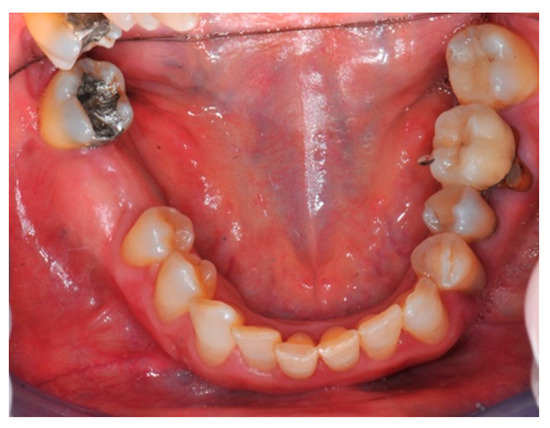

- Flap design: Soft tissue management should be as accurate as possible. The design of the flap should ensure a tension-free primary closure of the wound even after voluminous grafting of the defect. One option (preferred especially in wide vertical defects) is the execution of the so-called “poncho” flap. This technique includes a high vestibular incision of the mucosa, muscle and periosteum in order to undermine the preparation of the flap and to achieve its mobilization, followed by a deep incision in the buccal area with two additional vertical incisions that are performed at an appropriate distance from the occlusal area and the site of augmentation. After the incision, the preparation of a muco-periosteal flap and the remotion of scar tissue, a full thickness flap is raised until the bone defect is uncovered [17,18,19,20]. Finally, the positioning of the customized titanium mesh is passively tested to evaluate its fit intra-operatively (Figure 2, Figure 3, Figure 4 and Figure 5).